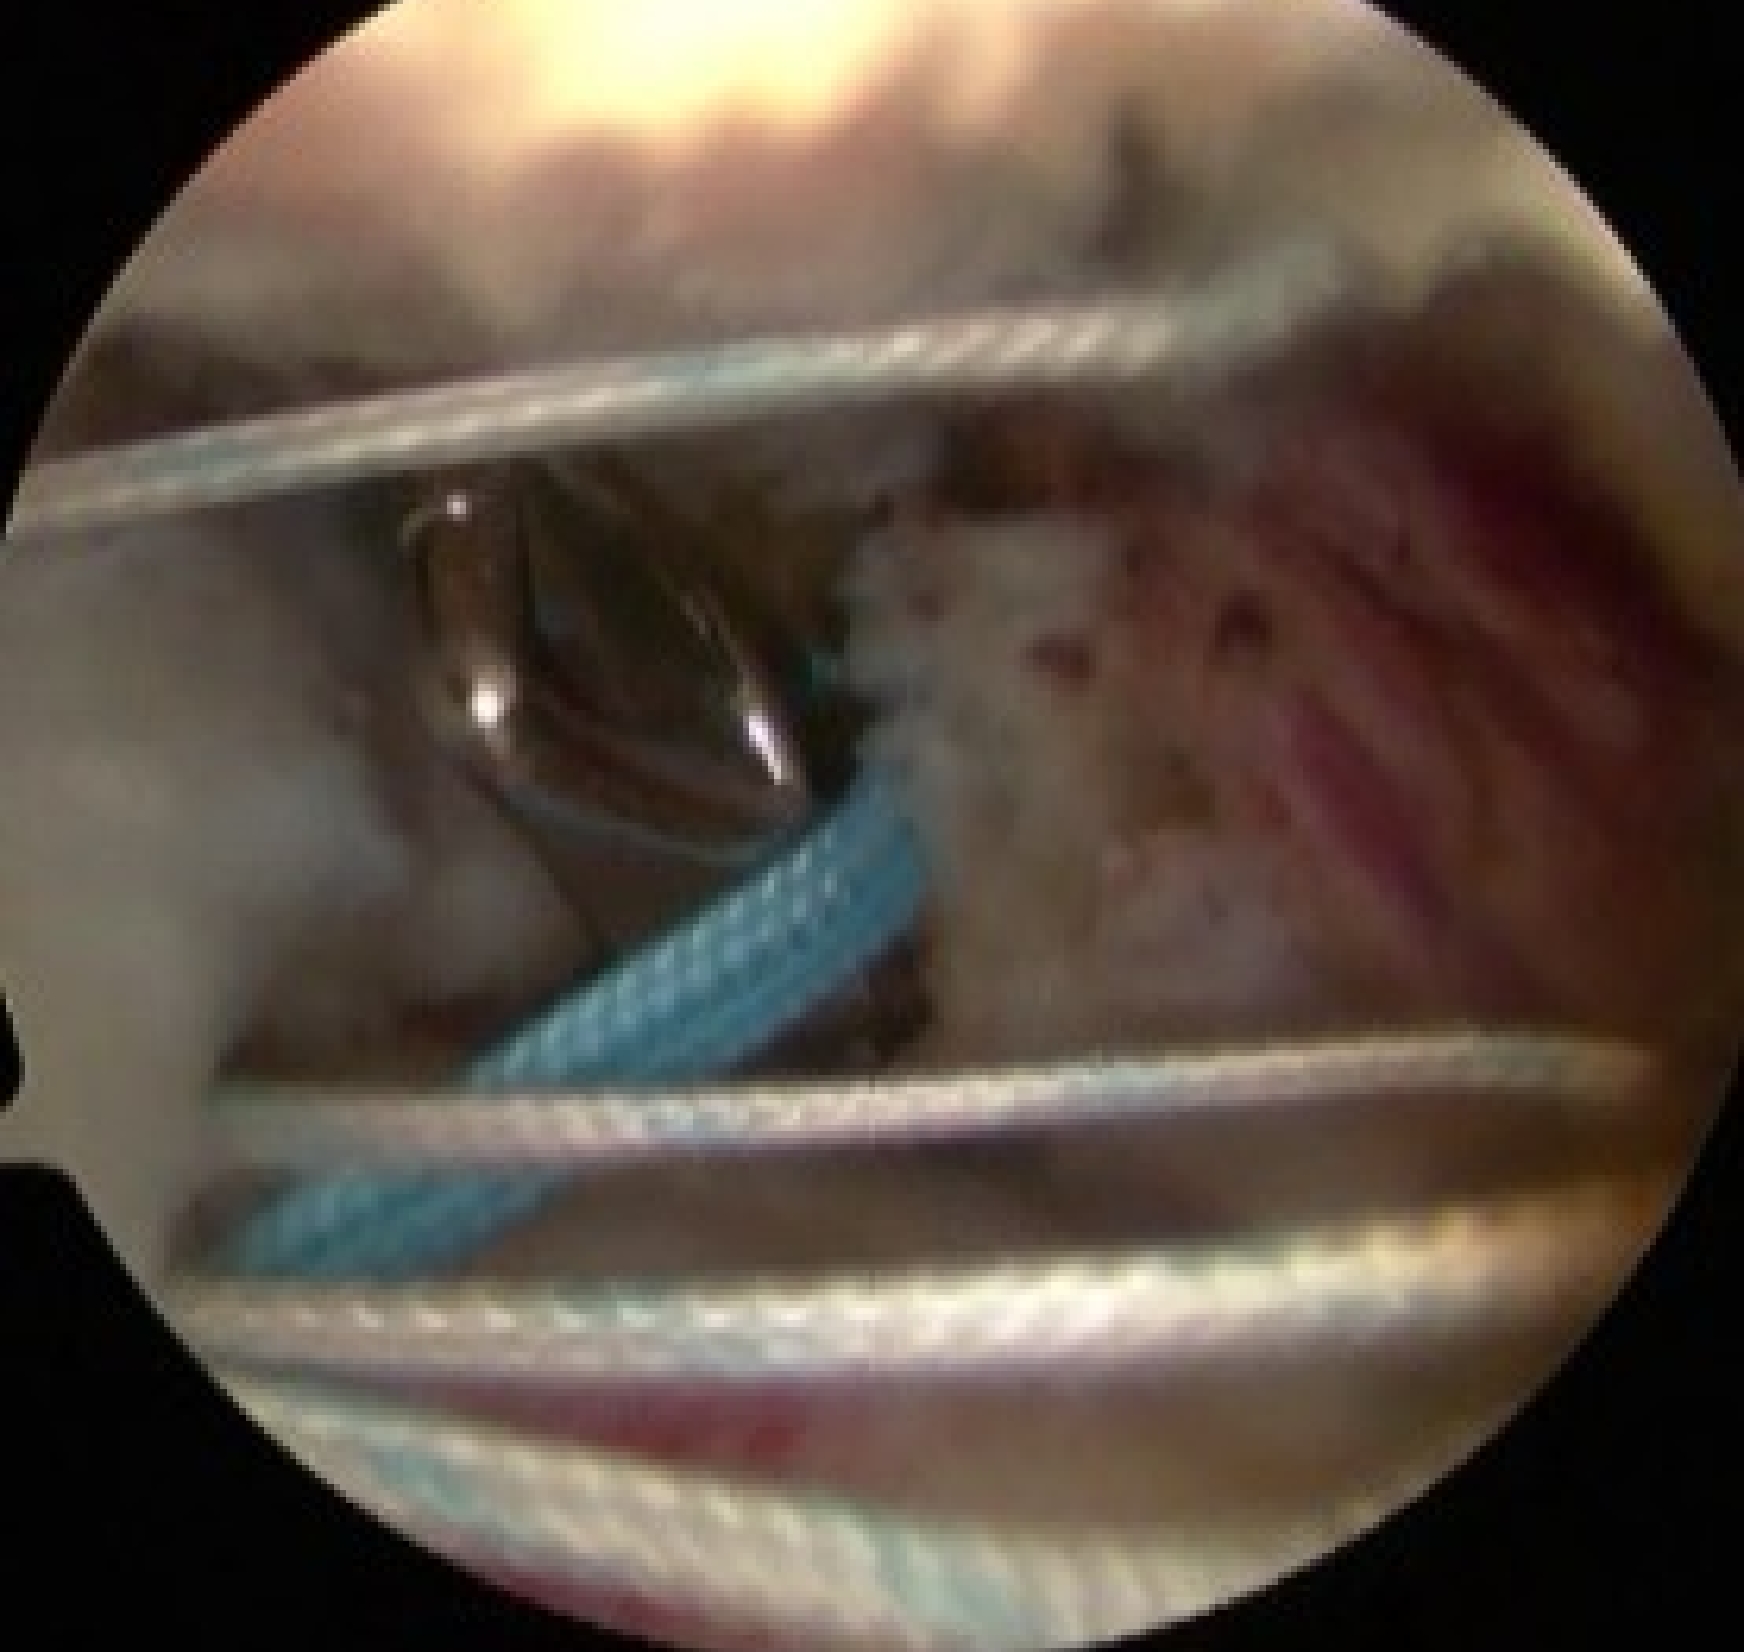

内側アンカー設置

吸収性アンカー(直径4.5から5.5mm)

器具を使用して腱板に糸をかける

外側アンカー設置